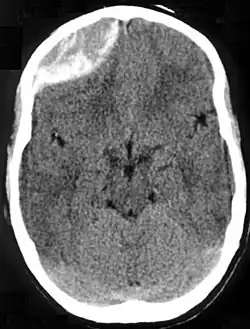

![]() | |

| Epidural hematoma as seen on a CT scan with overlying skull fracture. Note the biconvex shaped collection of blood. There is also bruising with bleeding on the opposite side of the brain. | |

Epidural hematomas usually appear convex in shape because their expansion stops at the skull's sutures, where the dura mater is tightly attached to the skull. Thus, they expand inward toward the brain rather than along the inside of the skull, as occurs in subdural hematomas. Most people also have a skull fracture.[3]